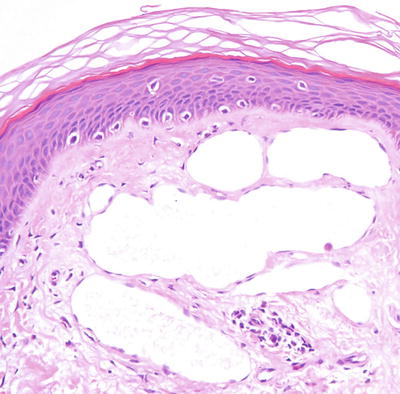

21.3.1.2 Histology

Histologic features of microcystic lymphatic malformation include an epidermis that is focally atrophic with elongated rete ridges that extend down and surround superficially located and dilated vascular channels [65–67]. The epidermis directly overlying the vascular channels is often atrophic, but rare cases of verrucous epidermal hyperplasia with papillomatosis and acanthosis have been described [66, 68]. The ectatic vessels are thin-walled and lined by flattened endothelial cells (Figs. 21.6 and 21.7). The spaces are often filled with eosinophilic proteinaceous material. When traumatized, hemorrhage into the vascular spaces may be present. Lymphocytes surround the dilated vessels in some cases. Dilated lymphatic spaces may extend into the deeper dermis and subcutaneous fat, but this feature is not seen on all biopsies [65, 67, 69, 70]. Ultrastructural analysis has suggested that the primary pathology of these lesions resides in the deep and enlarged malformed vessels, and the superficial vessels represent secondary changes of long-standing lymphostasis [71].

Fig. 21.6

Within the superficial dermis, large thin-walled, and dilated vascular channels are surrounded by acanthotic epidermis in lymphangioma circumscriptum

Fig. 21.7

Vessels are lined by flattened endothelial cells and often do not contain erythrocytes in lymphangioma circumscriptum